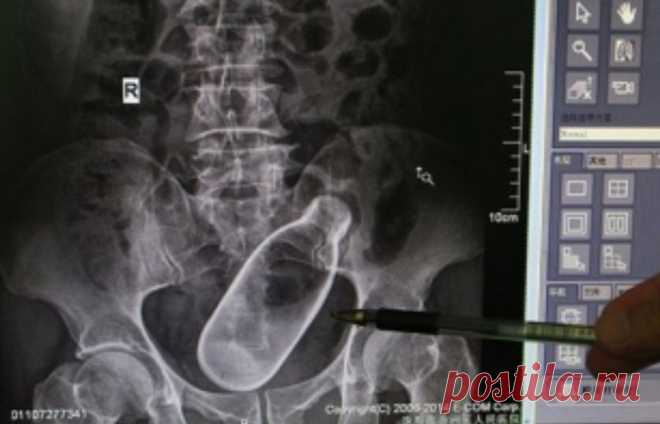

9 неожиданных предметов, которые врачи извлекли из пациентов

У Вас тут в бутылка...

Хирургов по праву можно считать настоящими волшебниками – они возвращают людей к жизни. Причём порой случается, что люди оказываются на операционном столе по весьма странным …